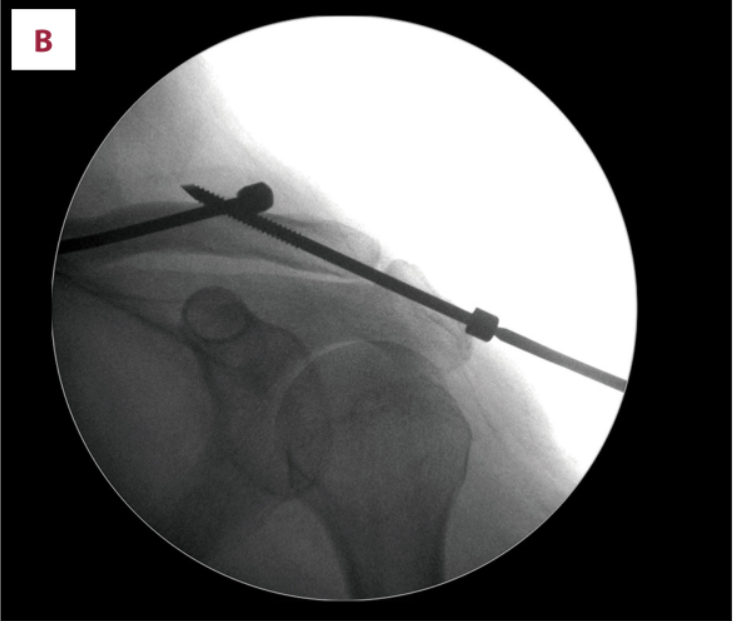

(A)在c臂图像增强器的帮助下,用克氏针将锁骨推入解剖位置进行闭合复位。(B)从肩峰尖端穿过肩锁关节(ACJ)至锁骨远端,用Knowles钉在锁骨远端后侧实现皮质锚定。采用Knowles销固定时,采用拉力螺钉技术保持ACJ空间。(C)术后x线片显示经皮Knowles针闭合复位治疗ACJ脱位复位良好。